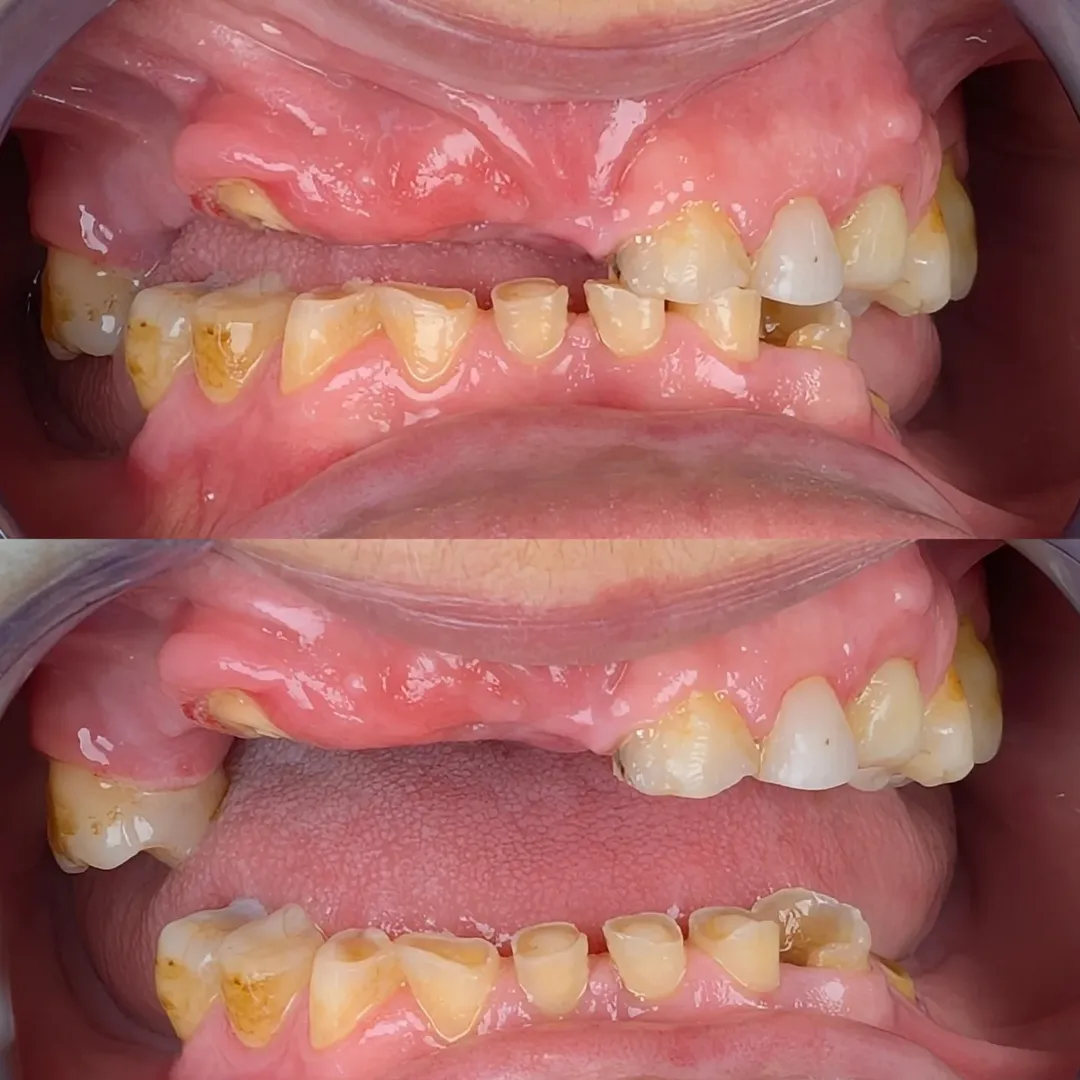

Nas imagens iniciais, vemos claramente o impacto do desgaste e da perda dentária.

Dentes fraturados, alterações no sorriso e uma grande limitação funcional e estética. A simples colocação de próteses convencionais resolveria parcialmente o problema, mas traria desconforto e necessidade de ganchos visíveis, algo que tento sempre evitar.

No slider de imagens, conseguimos acompanhar o processo completo: